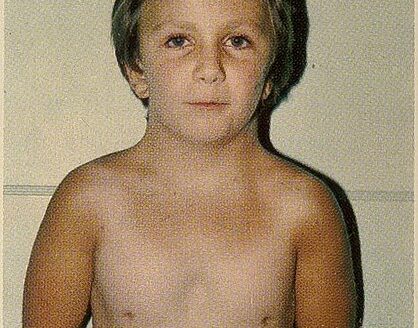

نشانگان ترنر

نشانگان یا سندروم ترنر یک اختلال ژنتیکی نادر است که تنها در خترها دیده میشود. می تواند سبب مشکلاتی از کوتاه قدی کرفته تا مشکلات قلبی شود. گاهی علائم آن قدر خفیف…